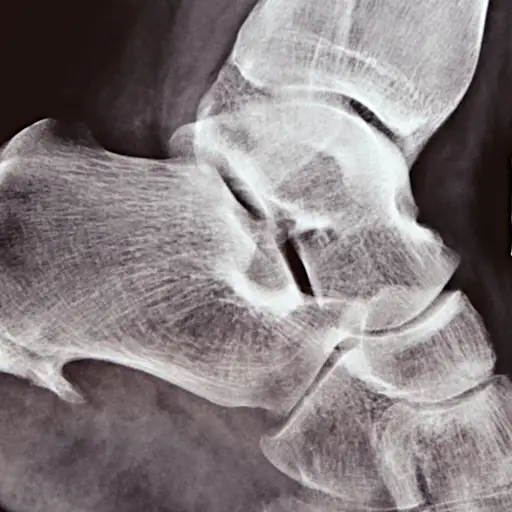

骨刺

当软骨磨损时,骨细胞被激活,在受影响的关节周围产生新的骨块,称为骨赘,或“骨刺”。弗兰克博士解释道:“身体想要再生软骨,但它不知道如何再生软骨。因此骨刺开始形成。”骨刺可以发生在任何关节,但最明显的是手部。它们可能会影响最靠近指尖的指关节,使其看起来比平常更大,几乎像肿了一样,但“肿”是硬的,不是软的。斯坦因博士说,你可能看不到其他关节的骨刺,但可以在X光片上看到。

陈博士说,在进行医疗历史后,您的医生将看看您的关节并检查炎症的迹象并检查炎症(温暖和肿胀)的症状,这可能表明炎症性关节炎等炎症性关节炎。如果可以在手或膝盖中可以易于使用,它们也可能觉得骨骼马刺患者。他们将通过移动关节来检查您的动作范围,让您的肌肉放松(排除肌肉疼痛作为原因)。X射线可以通过揭示骨骼之间的空间缩小,软骨丢失的迹象来帮助确认诊断。如果您的症状和X射线结果与OA系列,通常会进行诊断。